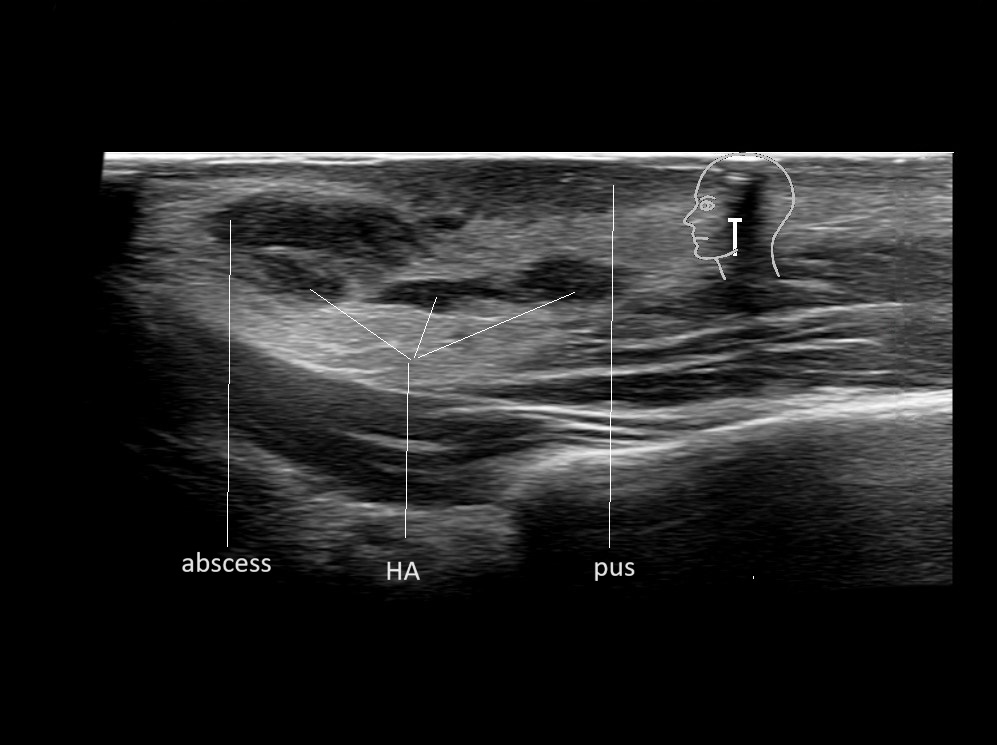

Filler injections in the parotid gland may go unnoticed, however, inflammatory reactions and abscesses may occur. Hypervascularity can be seen with color doppler. Filler deposits are supposed to be injected into the superficial fatty layer . The space to inject into this layer may be limited. Routinely we measure a width of 2-4 millimeters with sometimes subcutaneous layers being less than one millimeter thick.

Study the first image to recognize the different layers. If you are sure about the layers, swipe to the second image to view the answer (if applicable).